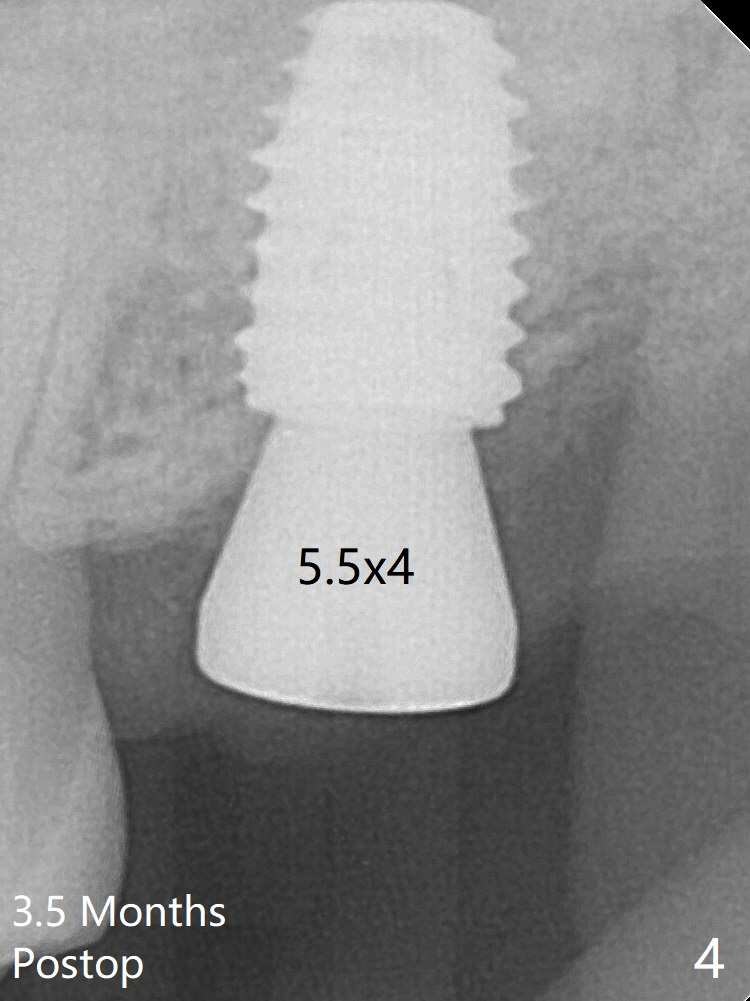

With sensor I, there is less distortion and angulation (Fig.4, as compared to Fig.1 (sensor II)).   A 5.5 mm profile drill is used prior to healing abutment placement.